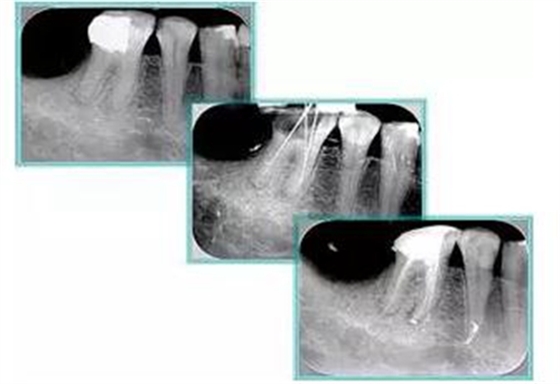

共有 4 張 X 線(xiàn)片,分別是術(shù)前、診斷絲 、主牙膠尖確認(rèn)、術(shù)后。

( 1 )術(shù)前:術(shù)前 X 線(xiàn)片用來(lái)了解牙齒的大概情況。術(shù)前預(yù)期為多根牙時(shí) X 線(xiàn)片應(yīng)偏頭拍攝。

( 2 )診斷絲:根據(jù)術(shù)前 X 線(xiàn)片進(jìn)行開(kāi)髓、根管的初步預(yù)備后,需要插入診斷絲,用來(lái)指示工作器械位置。常用 10 號(hào)或 15 號(hào)擴(kuò)大器作為診斷絲插入牙髓腔。

( 3 )主牙膠尖確認(rèn):通過(guò)術(shù)前預(yù)期和診斷絲診斷,明確工作長(zhǎng)度、牙根走向,進(jìn)行根管預(yù)備。之后應(yīng)進(jìn)行主牙膠尖(中銼)確認(rèn),已明確根管是否適合充填。

( 4 )術(shù)后:觀察治療效果。

6. 術(shù)后 X 線(xiàn)片

術(shù)后 X 線(xiàn)片用來(lái)評(píng)定根管充填 長(zhǎng)度、致密度(管壁清晰、側(cè)枝)等指標(biāo)。

左圖為根管充填術(shù)后 X 線(xiàn)片。圖中可見(jiàn),根管充填較好。右下圖有白色小點(diǎn),為側(cè)方加壓導(dǎo)致糊劑擠出所致,表明根管充填比較致密。